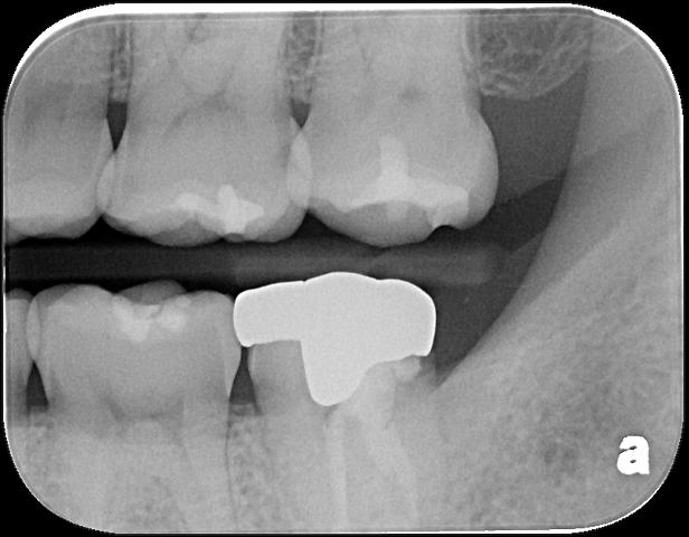

蛀牙未到牙髓

崁體製備,雷射牙齦修整